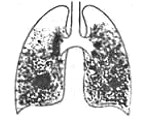

Рентгенография легких при силикотуберкулезе может отражать различную картину: на фоне диффузного крупно-сетчатого фиброза и типичных для силикоза симметричных узелковых высыпаний в средних и нижних долях появляются туберкулезные очаги, инфильтраты, силикотуберкуломы, каверны, преимущественно расположенные в верхушечных областях. Достоверность диагноза подтверждается при обнаружении МБТ в мокроте или промывных водах бронхов. Бронхоскопия помогает визуально определить пылевую пигментацию и признаки туберкулезного поражения слизистой бронхов.